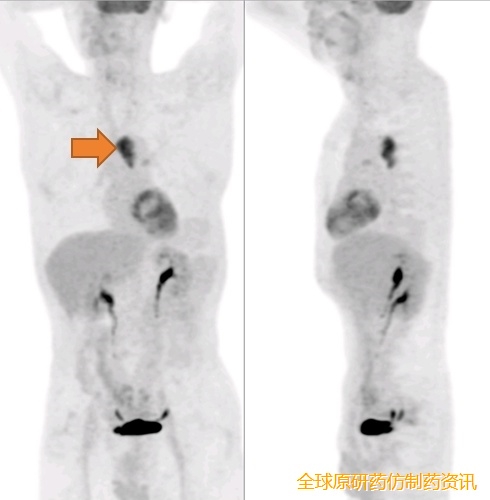

2024-07-10,PET-CT示:左侧胸腔胃,吻合口区FDG代谢未见增高;后纵膈不规则形软组织影,FDG代谢异常增高,SUVmax=7.6,与气管、降主动脉、胸椎前缘界限模糊,前方气管受压、向气管内突入,考虑食管癌术后转移,累及气管、降主动脉、胸椎前缘。

图1 影像学检查(2024-07-10)